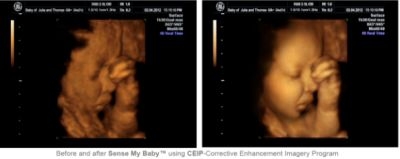

She continues, “The most amazing aspect of our CEIP (Corrective Enhancement Imagery Program) is that the mother doesn‘t require a special scan, any regular 3/4D scan is all that’s needed. The system is able to re-engineer existing imagery to create an ultra-clear image, allowing you ‘for the first time’ to see your unborn baby from within the womb with remarkable detail. It's the closest thing to seeing your baby before birth.”

Using ‘structural’ information from the original image, data characteristics are analysed and the system is able to differentiate between the degraded image area and that of a higher resolution - the latter being the area that is isolated and then captured. These images are then individually enhanced using CEIP, before being re-engineered to create a layering effect - where required the orientation of the image is changed to facilitate the reconstruction.